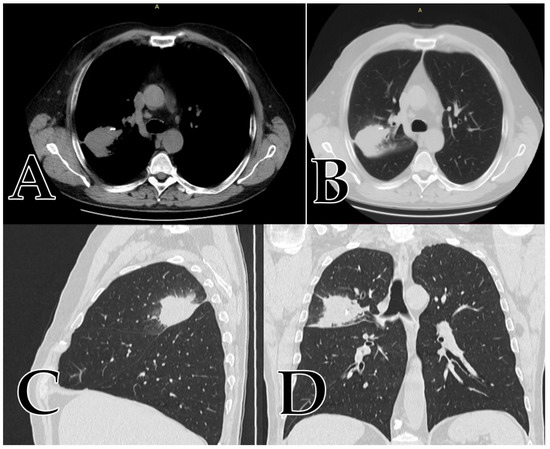

At the time of admission, the patient’s general status was worse, having symptoms such as a productive cough, fatigue, and dyspnea. The CT scan showed an increase in the diameter of the mass by 5 cm, having all the characteristics of a malignant lung tumor (Figure 3A–D), just as we described them for our study, see Figure 3 below.

Figure 3.

(A,B) coronal view; (C) sagittal view; (D) axial view of a right upper lobe mass presenting all the aspects of malignancy: size over 5 cm, gross spiculation, attenuation alternances (part solid, part GGO), punctuate calcification, no tumoral fatty tissue, positive bronchial sign with a mean value of 34 HU and a growth rate of 5 cm over 6 months period.